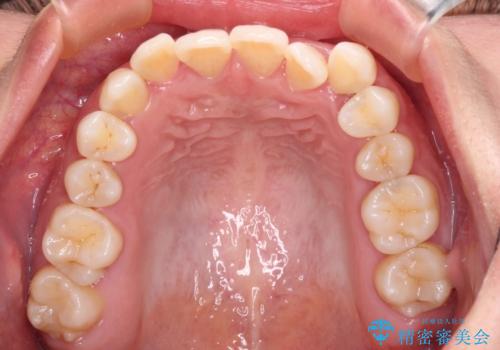

前歯の反対咬合 急速拡大装置とワイヤー装置であっという間の矯正治療

- 全顎的なクロスバイトと反対咬合を気にして来院された患者様です。

骨格的に下顎が前方位にありましたが、歯並びにより下顎が本来の位置よりも前方位に誘導される咬み合わせとなっていました。

上顎歯列および上顎骨が下顎に対して狭小であることが原因であるため、上顎の急速拡大装置を使用して上顎骨を側方に拡大することで反対咬合を改善し、ワイヤー装置で歯列を整えることとしました。

上顎の拡大に伴い反対咬合があっという間に改善されました。

元々の歯列不整は軽微であったため、僅か1年の期間で治療を終えることができました。